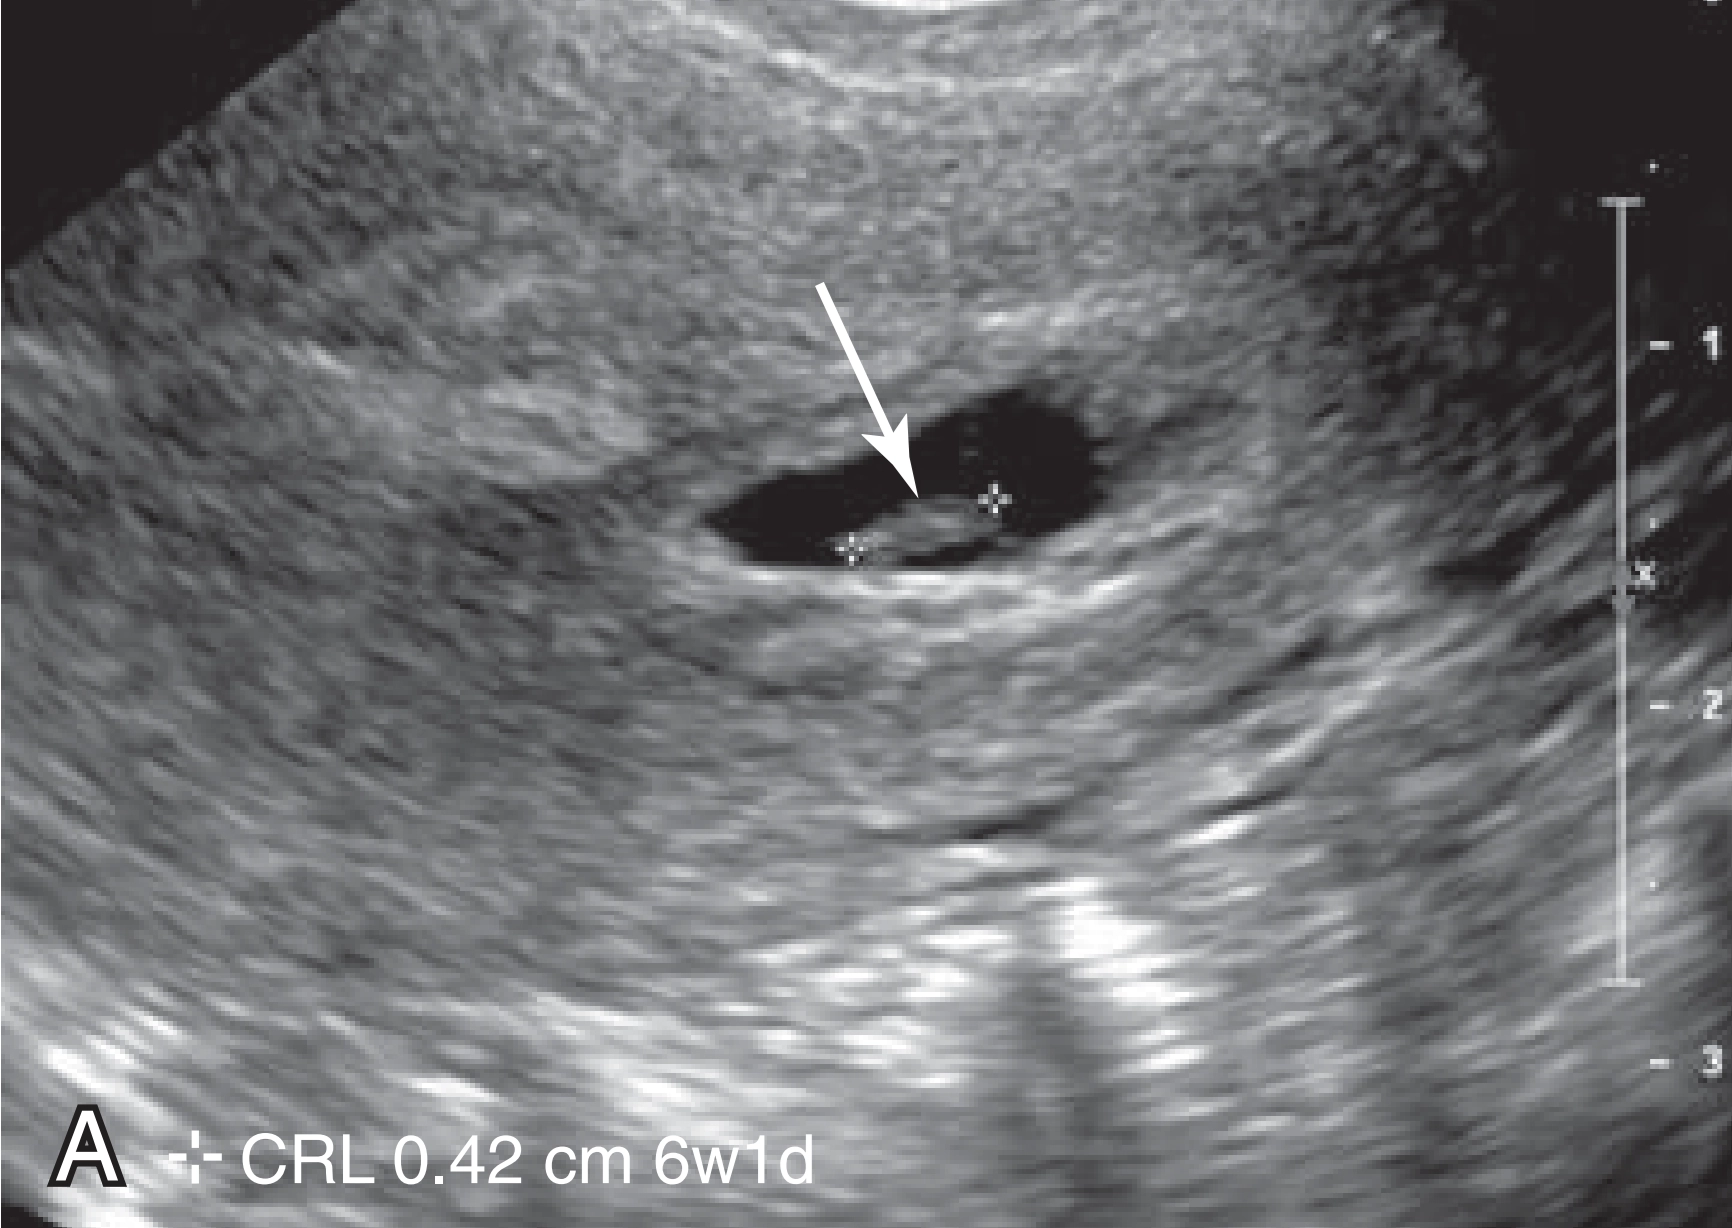

Tiêu chuẩn chẩn đoán thai ngừng phát triển (Sẩy thai quý I)